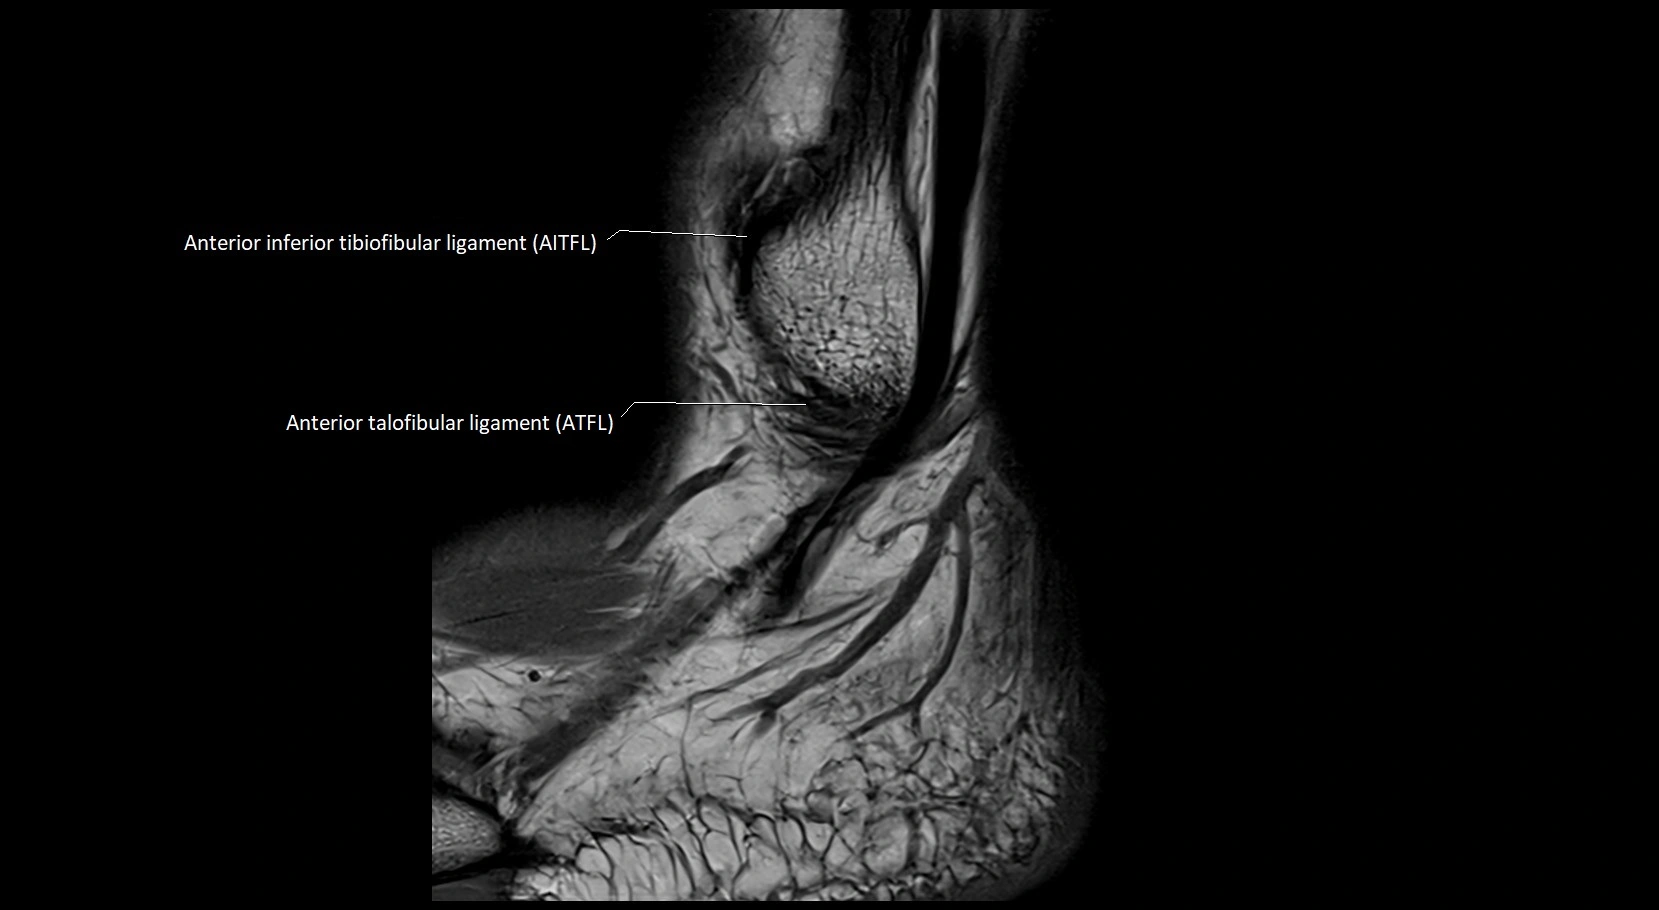

MRI image

image